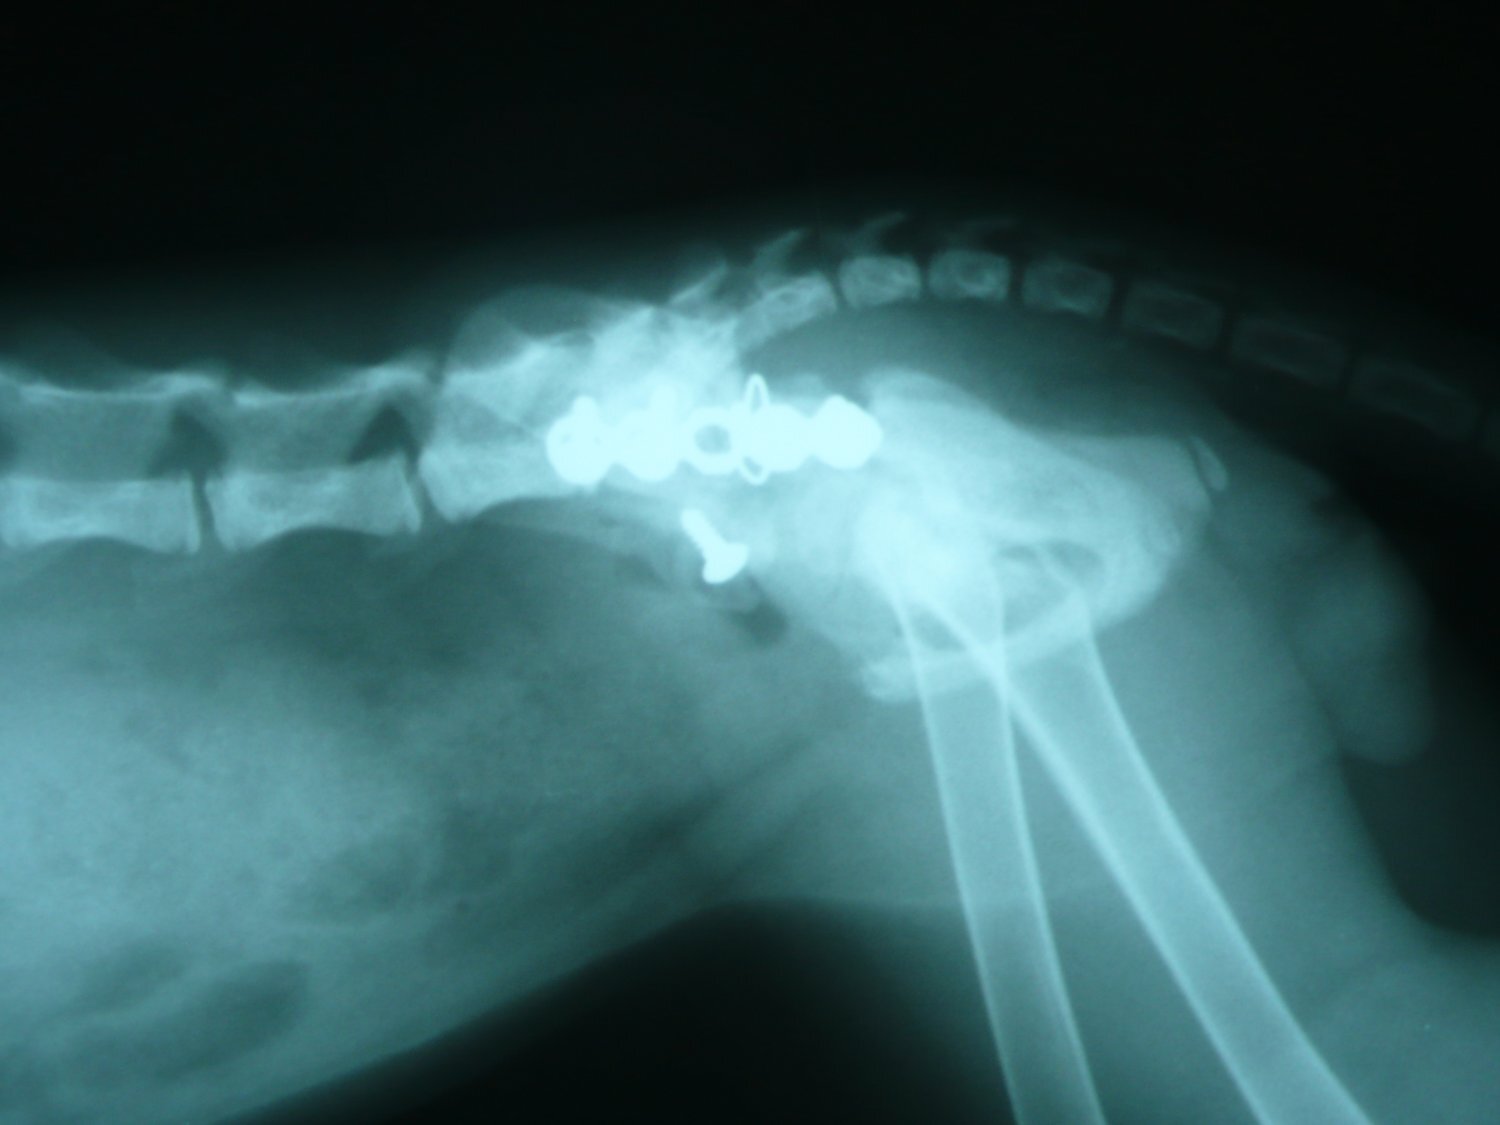

主題: 大龍街骨盤骨折橘白貓第二次醫療 申請者姓名: Akimasa Tu 花色: 申請日期: 2013-01-10 01:15:09 申請者部落格: 申請者臉書網址: https://www.facebook.com/akimasa.tu 所在縣市/合作醫院: 台北市/長沁動物醫院 治療費用: 10000元 需求人數: 22人 已結案 (2013-02-23 11:57:47) 報名人員: Julling Hu(已付款)、speciallucky(已付款)、Mau Lin(已付款)、阿麥麥(已付款)、李安妮(已付款)、Lichen Cheng(已付款)、J2(已付款)、Diamond Wu(已付款)、Monica Hu(已付款)、孫小晴(已付款)、Joyce Shih(已付款)、Lynn Lin(已付款)、Ray Lei(已付款)、Chinling Ho(已付款)、Shirley(已付款)、Shirley(已付款)、fenny(已付款)、yun(已付款)、yun(已付款)、yun(已付款)、yun(已付款)、yun(已付款)、 候補人員: 然後勒、 動物病情說明: 這隻是在大同區大龍街被救援的小貓,疑似被狗咬傷的小貓,之前因為

骨盤骨折,無法排便,而進行手術,術後先帶回照顧,原本食欲及活動

力都很正常,但一段時間後,看他常常好貓砂,但又沒大便,幾天後不

吃東西,帶回原手術醫院檢查,發現他肚子又是大便,而且手術固定的

骨板,螺絲鬆脫了!

可能是腸子蠕動不良,或鬆脫螺絲導致無法排便,因骨盤已固定,所以

院方決定將鬆脫螺絲及骨板再次開刀移除,術後活動力及食欲又恢復正

常,目前又先帶回照顧,因同時間又另一隻小貓得了貓瘟,為求保險起

見,也一並幫他注射了第一劑的三合一疫苗。